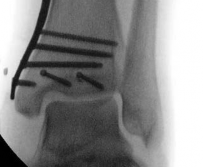

Fibular Fixation Strategy

The role of fibular fixation in distal tibia fractures remains a topic of academic debate, but in the context of intramedullary nailing, it is often a highly valuable adjunct. Plating the fibula restores the length of the lateral column and corrects rotational malalignment, effectively converting a highly unstable distal tibia fracture into a more manageable, length-stable pattern.

Image

Fibular fixation is typically performed prior to tibial nailing. An open reduction and internal fixation utilizing a one-third tubular plate or anatomic distal fibula plate is standard. By stabilizing the fibula, the tendency for the distal tibia to drift into valgus during nail insertion is significantly mitigated.